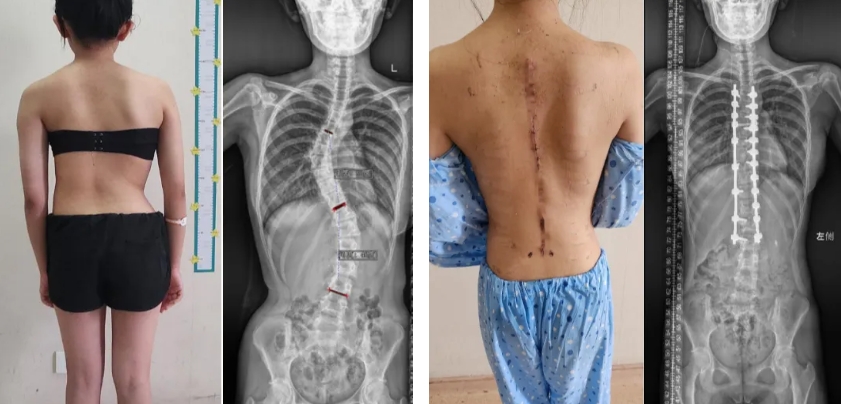

13岁的小林(化名),9岁时发现特发性脊柱侧弯,初始侧弯最大角度33°,患者佩戴支具外固定治疗,但仍未能阻止病情的进展。小林10岁时复查,发现侧弯度数仍有增大,并出现腰背部频发疼痛等症状,侧弯度数持续性加重。小林在家人的陪同下,由邱勇院士主刀进行了脊柱侧弯的矫形手术,手术顺利,小林术后感觉腰背痛已经明显减轻,畸形已恢复,目前随诊1年余,病情稳定,且无并发症发生。